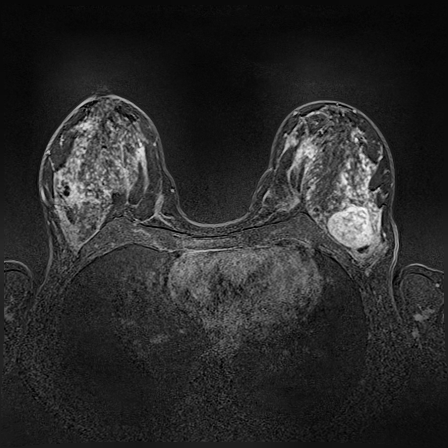

MR images for this study were acquired on 1.5 T scanners Magnetom Avanto and 3.0 T Magnetom Verio, Siemens Healthineers, Erlangen, Germany, with dedicated breast array coils and the patient in a prone position. The contrast media was applied into the cubital vein after the first of six dynamic acquisitions with a flow of 1.0 mL/sec chased by a 20 mL saline flush. One hundred and six lesions were identified from a representative set of DCE-MRI exams from 80 female patients by two expert radiologists who have 7 years of experience in evaluation of clinical findings. The mean patient age was 50 13 and based on histopathologically 42 of the lesions were diagnosed as benign and the remaining 64 as malignant.

The proposed method starts with selecting a particular slice of breast MRI volume, performed by an expert radiologist, such that it contains at least one lesion. The slice image is normally the subtraction of pre-contrast and post-contrast images. The ground truth segmentation provided by expert radiologists and ROI is drawn around the lesion manually. As a pre-processing step, We applied contrast limited adaptive histogram equalization (CLAHE) [12] on that particular slice globally to improve lesion contrast. Then we computed the morphological gradient of the image, which is the point-wise difference between a unitary dilation and erosion.

In MR images, tumor regions are normally brighter and have more uniform intensity than the neighbouring healthy tissue. Based on this fact, we determined the internal and external markers by sorting out the pixel values in ROIs in descending order and chose pixels with maximum intensity values as markers. After selecting the markers the normal watershed transformation is applied on the ROIs image which is shown in Fig 1 Finally, a binary mask is generated based on watershed output regions. However, we identified the optimal number of markers based on segmentation accuracy evaluated using Dice and Jaccard.